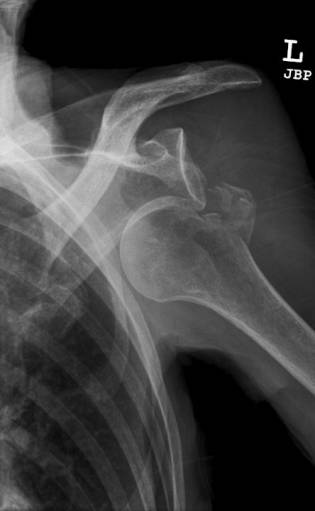

bankart骨折

bankart骨折指肩关节盂前下边缘骨折,伴或者不伴有肩关节前脱位。是肩关节盂唇前下方在前下盂肱韧带复合体附着处的撕脱性损伤。因肩关节前脱位引起,是造成习惯性前方不稳定和脱臼的基本损伤。

Hill-Sachs骨折

Hill-Sachs骨折指肱骨头压缩性骨折,当肩关节前脱位时,关节盂前缘撞击导致肱骨头后外侧压缩骨折。